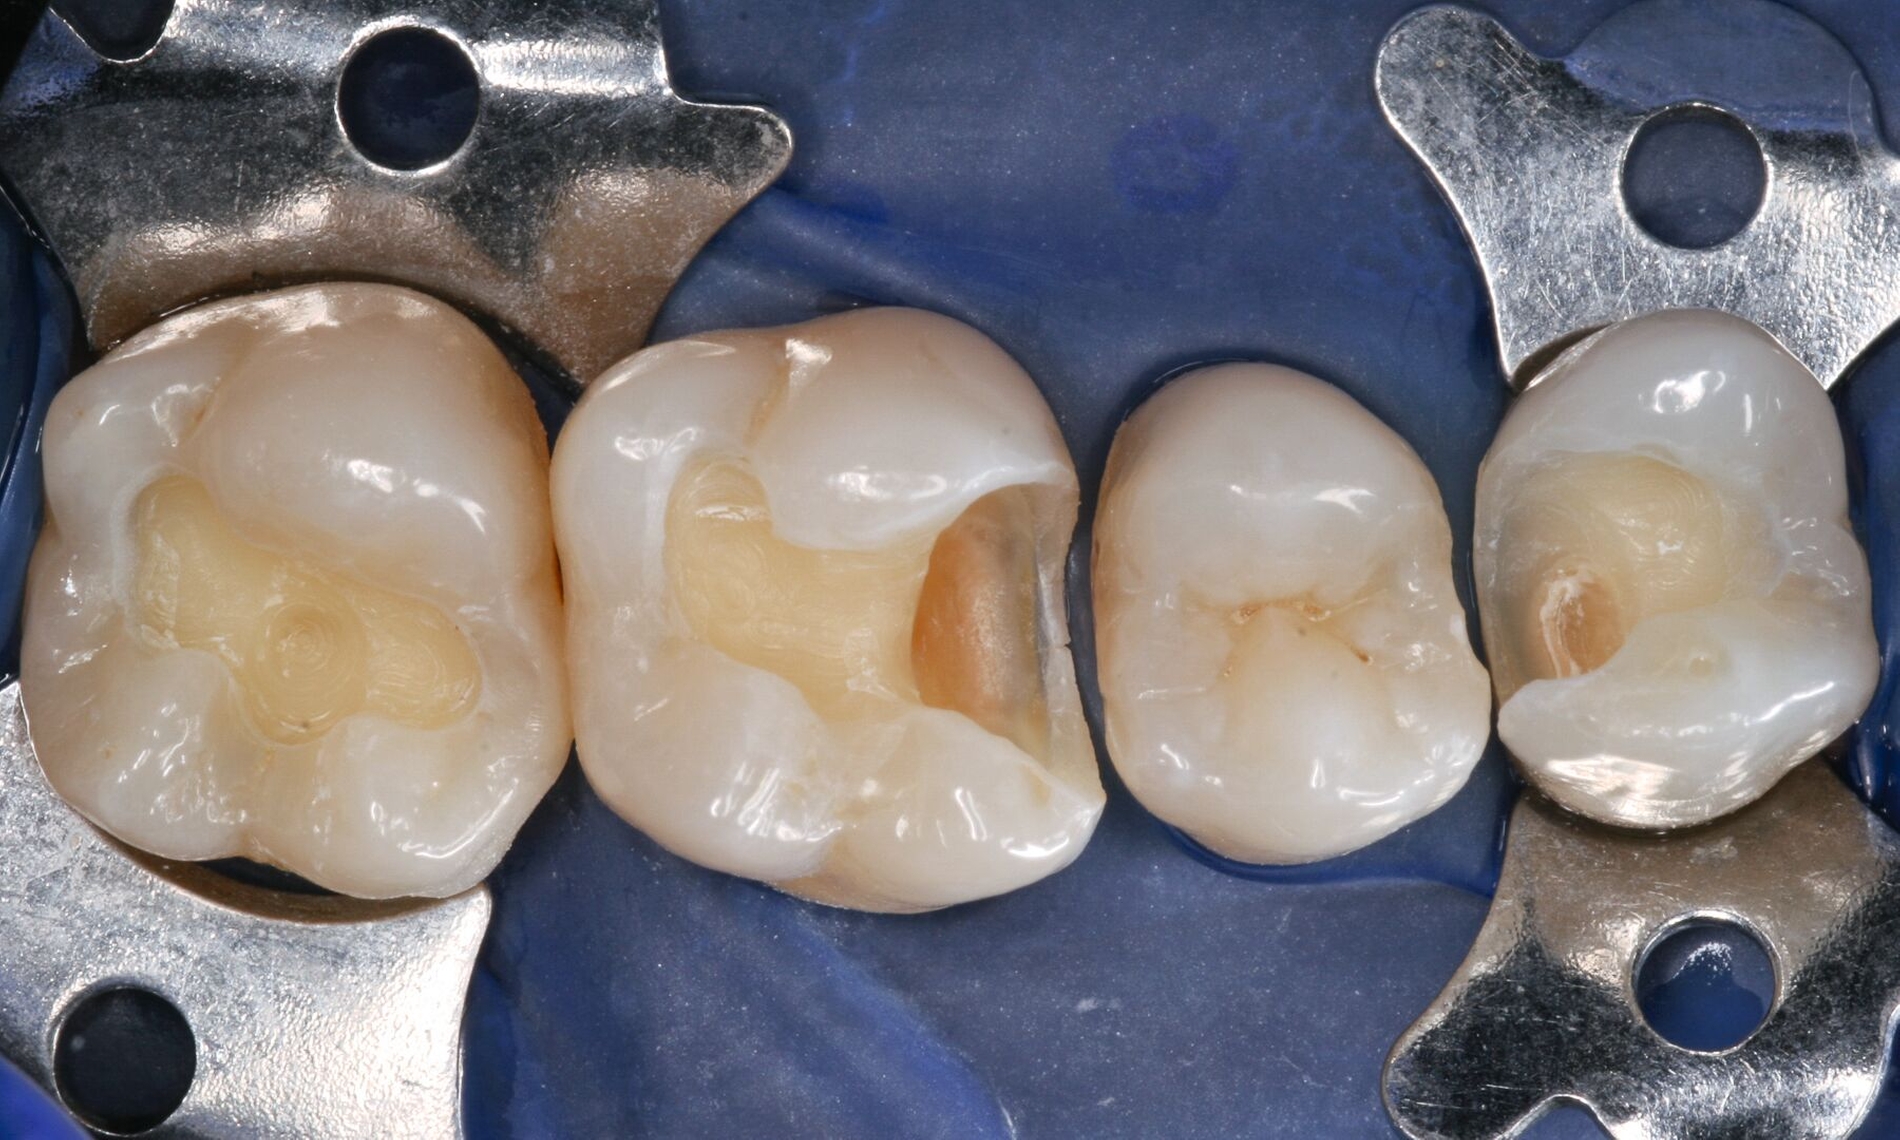

Für solche tiefen Areale existieren zwei unterschiedliche Lösungsansätze: Entweder man exkaviert einfach weniger aggressiv [Schwendicke et al., 2013] oder man appliziert ausschließlich in diesen Bereichen kleine Mengen klassischer „Cp-Medikamente“ oder Kalziumsilikatzemente [Schmidt et al., 2020] im Sinne einer kleinen Unterfüllung zur Blockade der „Tags“ [European Society of Endodontology, 2019]. Der weniger tief exkavierte Rest der Kavität wird aber auch hier vollständig mit einem Adhäsivsystem versiegelt und nicht mit einer konventionellen Zementunterfüllung [Arandi et al., 2020; European Society of Endodontology, 2019]. Eine korrekte Indikationsstellung für die Applikation eines Cp-Materials ist jedoch wichtig, da diese Materialien die Gesamthaftung in der restlichen Kavität reduzieren können [Frankenberger et al., 2021]. Die adhäsive Dentinversiegelung stellt heute den wirksamsten Schutz des Pulpa-Dentin-Komplexes dar (Abbildungen 3 und 4) [Arandi et al., 2020]. Das Risiko, dass die Pulpa dadurch einen irreversiblen Schaden erleidet, ist äußerst gering und minimal im Vergleich zum Schädigungspotenzial eines Diamantschleifers, der bei Amalgam und Gold oftmals „im Gesunden“ statt rein minimalinvasiv verwendet werden musste [Olmez et al., 1995; Schweikl et al., 2017].